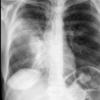

Case 2 Lingular pneum PA

Date: 04/17/2005

Views: 6058